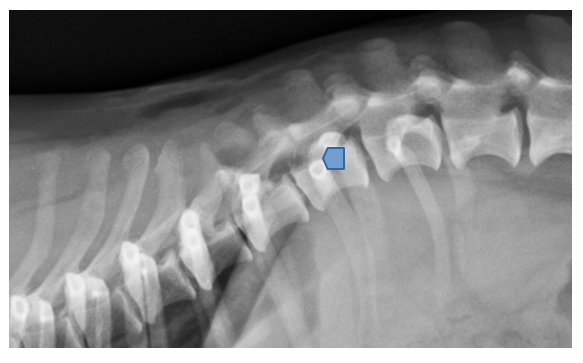

La columna presenta un buen alineamiento.

En el espacio intervertebral (IV) de T11-T12, se visualiza una lesión extradural, con presencia de material hiperatenuante (parcialmente mineralizado) localizado en el aspecto ventral del canal vertebral, lateralizado a la derecha (flechas azules).

Este material se extiende cranealmente a lo largo del cuerpo vertebral de T11 hasta su aspecto craneal, ocupando aprox. 50-70% del diámetro del canal vertebral, causando moderada/marcada compresión medular (flechas naranjas).

El material también se extiende hacia el foramen IV derecho de T11-T12.

Inmediatamente caudal a la lesión descrita, a nivel craneal del cuerpo vertebral de T12, se visualiza una leve cantidad de material hiperatenuante a la médula pre-contraste que la rodea (flechas rosas)

Lesión extradural lateralizada a la derecha en T11-T12, compatible con extrusión discal (hernia Hansen tipo I) con extensión del material discal cranealmente, a lo largo del cuerpo vertebral de T11 causando moderada/severa mielopatía compresiva.